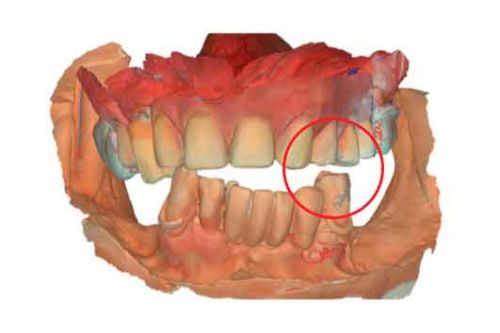

Picture - Initial bite situation

3D models - Bite scan from intra-oral scanner

In a typical digital workflow, the first step involves intraoral scanner (IOS) acquisition. However, in cases with insufficient references, obtaining an accurate bite can be challenging. Discover alternative methods to construct dynamic virtual patients, bridging the gap from initial situations to provisional solutions.